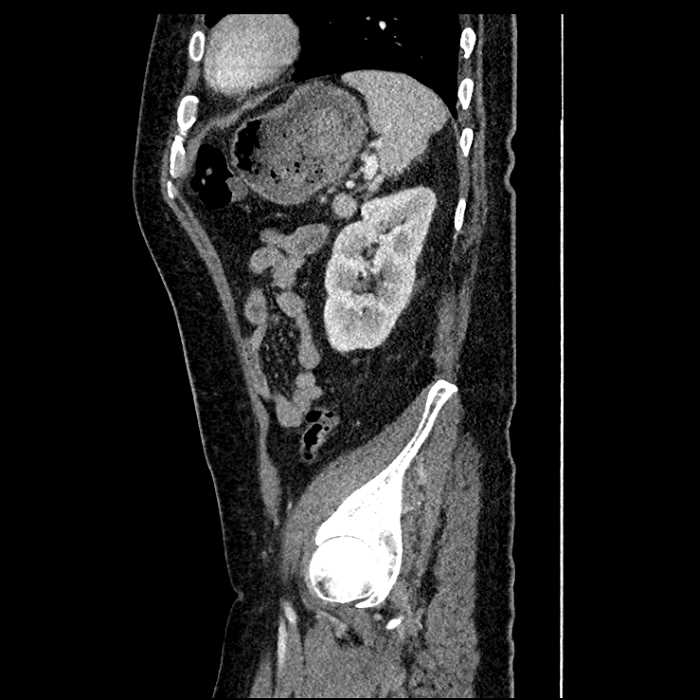

• Mild mural thickening of a segment of the sigmoid colon with adjacent fat stranding and a 1.5 cm fluid and gas collection along the tip of an inflamed diverticulum

• Loss of the normal fat plane between this collection and adjacent loops of small bowel, which demonstrate mural thickening

• No bowel obstruction

Acute sigmoid diverticulitis complicated by a small contained perforation and a large abscess in the right hepatic lobe. Additional small subcapsular abscesses along the anterior margin of the left hepatic lobe.

Additionally, loss of the normal fat plane between the peridiverticular collection and adjacent thickened loops of small bowel raises the potential for an enterocolonic fistula.

Hepatic abscess showing the double target sign with low density internally surrounded by a thin inner enhancing rim (red arrow) and ill-defined outer low density rim (yellow arrow). Blue arrow indicates an internal septation. Red arrows: additional smaller subcapsular abscesses. Red arrow: focal contained perforation associated with diverticulitis.